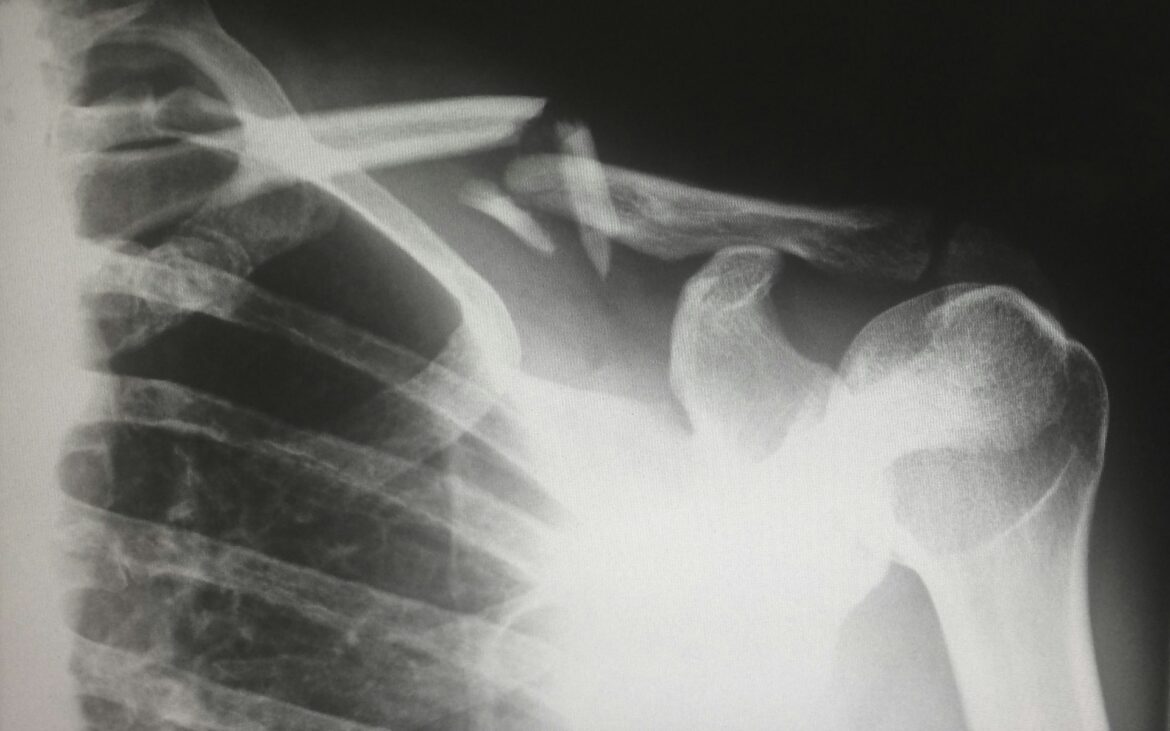

The worker sustained bilateral shoulder injuries on Jan. 14, 2021, while performing job duties. Medical imaging confirmed a full-thickness tear of the left supraspinatus tendon and a full-thickness tear of the right biceps tendon. The WCB accepted both injuries in April 2021.

The consultant acknowledged that some changes observed in the worker’s shoulders were likely degenerative in origin — including the circumferential labral tear in the left shoulder that was surgically debrided, and a labral tear in the right shoulder that did not require surgery. However, the consultant determined that these changes did not prolong the worker’s recovery. According to the Official Disability Guidelines, the expected return-to-manual-work timeframe for a supraspinatus tear is 70 to 90 days, and the worker was ready to return to work on a graduated basis within that window.